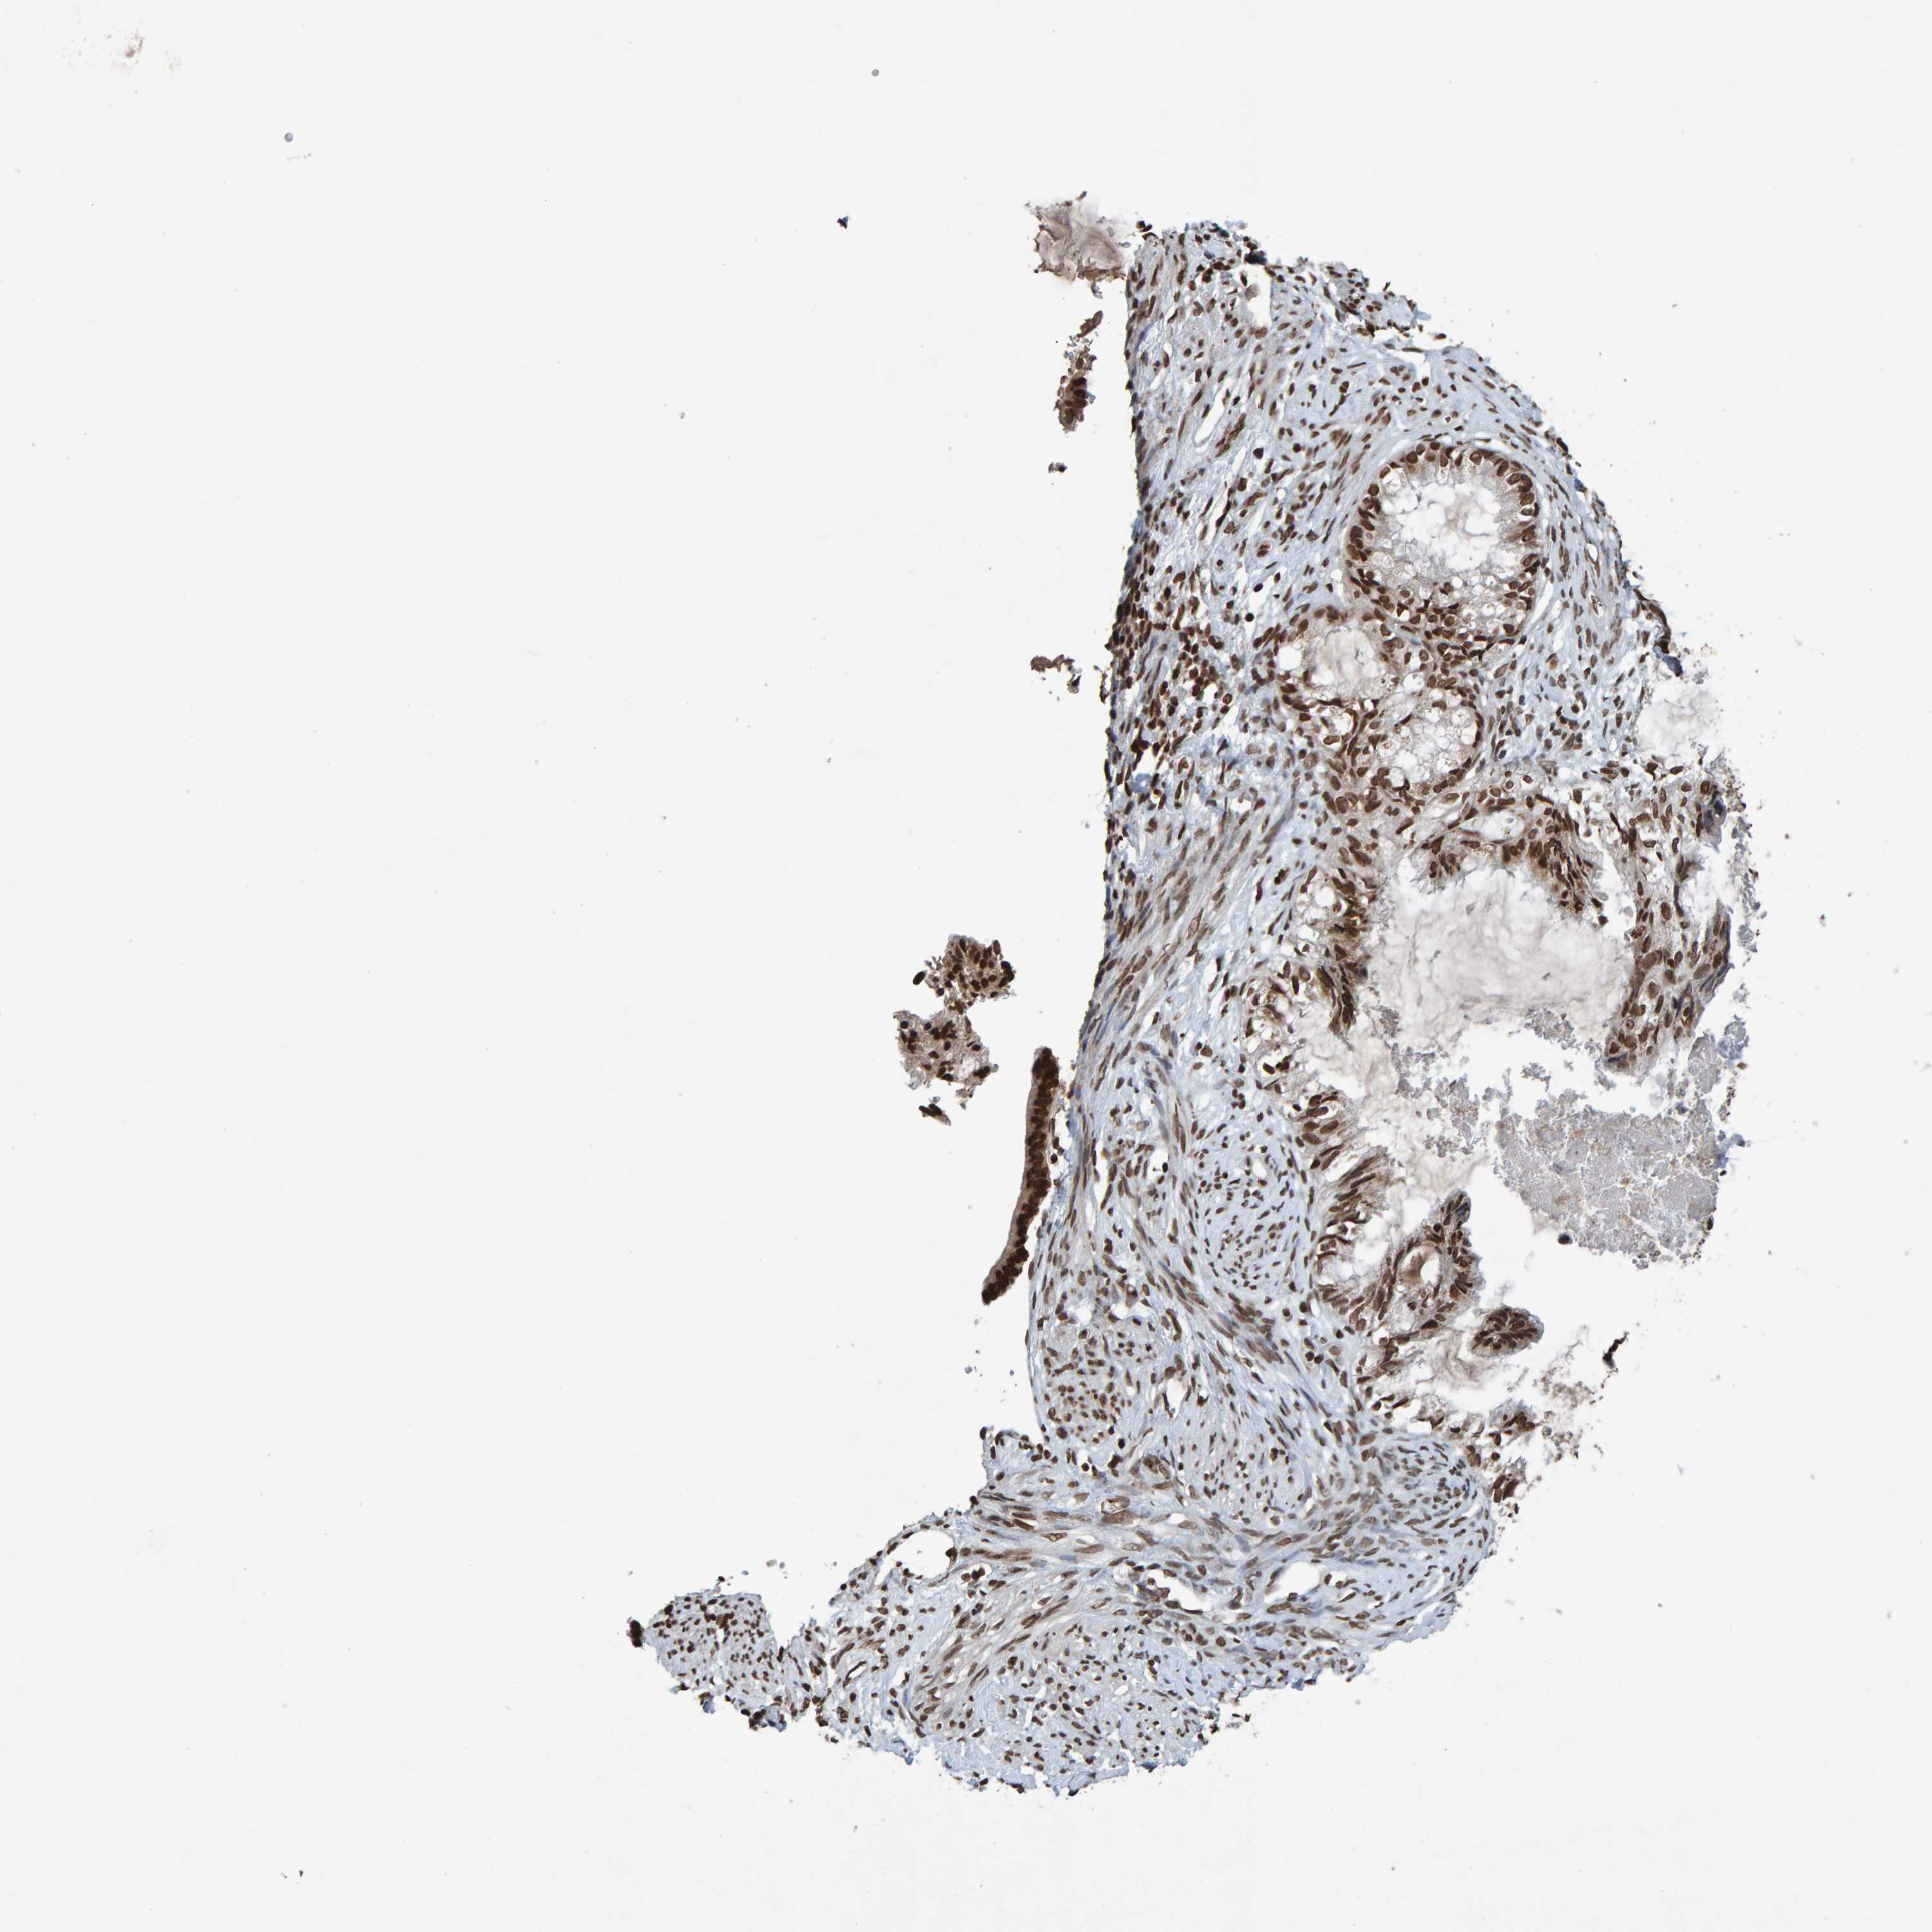

CERVICAL CANCER - Protein expressioni

A mouse-over function shows sample information and annotation data. Click on an image to view it in a full screen mode. Samples can be filtered based on level of antibody staining by selecting one or several of the following categories: high, medium, low and not detected. The assay and annotation is described here.

Note that samples used for immunohistochemistry by the Human Protein Atlas do not correspond to samples in the TCGA dataset.

Antibody stainingi

Antibody staining in the annotated cell types in the current human tissue is reported as not detected, low, medium, or high, based on conventional immunohistochemistry profiling in selected tissues. This score is based on the combination of the staining intensity and fraction of stained cells.

Each image is clickable and will lead to virtual microscopy that enables deeper exploration of all samples and also displays staining intensity scores, fraction scores and subcellular localization as well as patient and tissue information for each sample.

Antibody HPA057236

Antibody CAB022549

Staining

High

Medium

Low

Not detected

Intensity

Strong

Moderate

Weak

Negative

Quantity

>75%

75%-25%

<25%

None

Location

Nuclear

Cytoplasmic/membranous

Cytoplasmic/membranous,nuclear

Squamous cell carcinoma, NOS

Adenocarcinoma, NOS